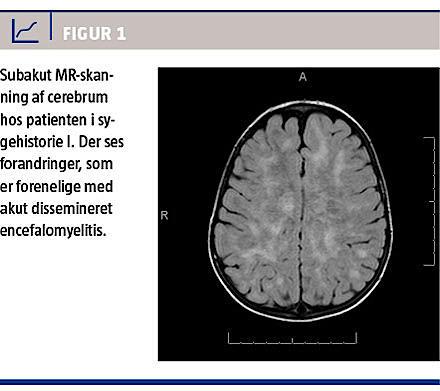

Dagen efter indlæggelsen blev der udført en subakut MR-skanning af cerebrum (Figur 1). MR-skanningen viste forandringer, som var forenelige med ADEM, hvorefter behandlingen blev suppleret med intravenøst (i.v.) givet steroid.

Efter otte mdr. blev der lavet en kontrol MR-skanning, som viste betydelig regression af de tidligere forandringer.